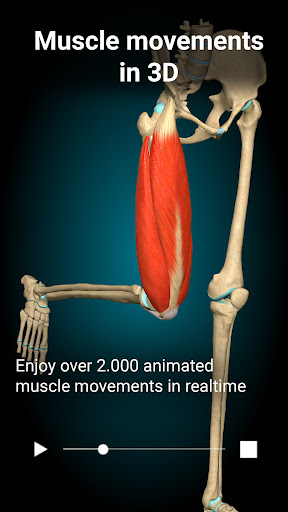

- Added more than 500 muscle movement animations

- Added more than 500 muscle movement animations

- Added more than 500 muscle movement animations

- Added more than 500 muscle movement animations